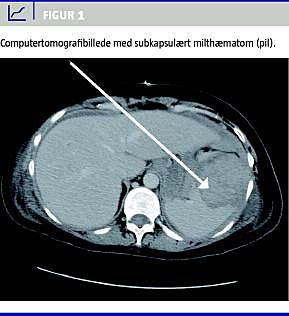

Under indgrebet blev der konstateret en større mængde såvel friskt som gammelt blod i abdomen, samt en tredjedel løsning af placenta. Da blødningskilden ikke kunne identificeres, blev den abdominalkirurgiske bagvagt tilkaldt. Under gennemgang af alle relevante strukturer blev der påvist en lille avulsion af miltens frie laterale kant. Der kunne ikke konstateres igangværende blødning, og fundet blev anført som et tidligere traume. Patienten var herefter somatisk stabil. Der blev foretaget CT med kontrast af thorax og abdomen, hvilket viste en grad III-miltskade, med et 5 × 7 cm intrasplenisk hæmatom og intakt kapsel (Figur 1 ).